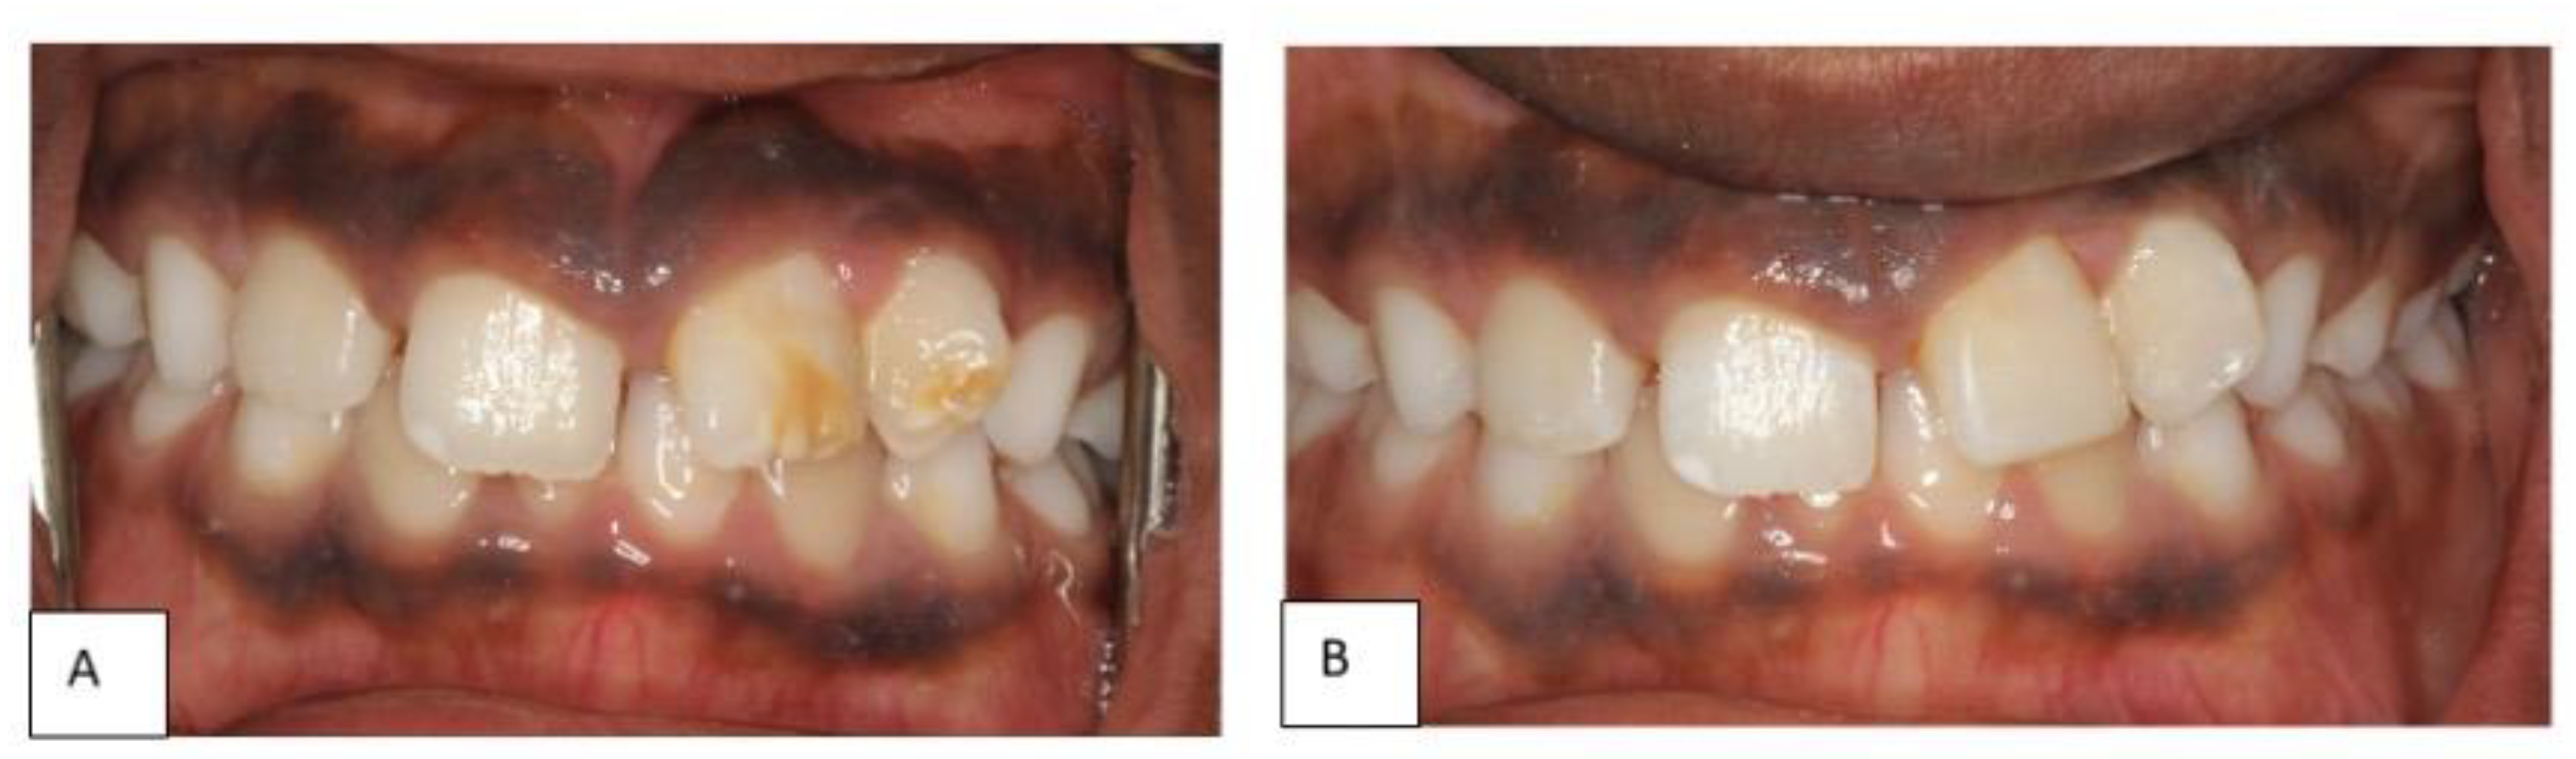

2.2. Treatment Plan and Progress